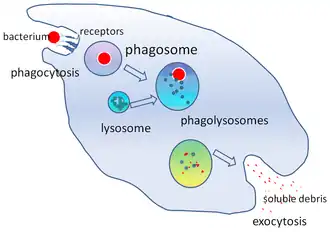

Phagocytosis is the process of taking in particles such as bacteria, invasive fungi, parasites, dead host cells, and cellular and foreign debris by a cell.[22] It involves a chain of molecular processes.[23][24] Phagocytosis occurs after the foreign body, a bacterial cell, for example, has bound to molecules called "receptors" that are on the surface of the phagocyte. The phagocyte then stretches itself around the bacterium and engulfs it. Phagocytosis of bacteria by human neutrophils takes on average nine minutes.[25] Once inside this phagocyte, the bacterium is trapped in a compartment called a phagosome. Within one minute the phagosome merges with either a lysosome or a granule to form a phagolysosome. The bacterium is then subjected to an overwhelming array of killing mechanisms[26] and is dead a few minutes later.[25] Dendritic cells and macrophages are not so fast, and phagocytosis can take many hours in these cells. Macrophages are slow and untidy eaters; they engulf huge quantities of material and frequently release some undigested back into the tissues. This debris serves as a signal to recruit more phagocytes from the blood.[27] Phagocytes have voracious appetites; scientists have even fed macrophages with iron filings and then used a small magnet to separate them from other cells.[27]